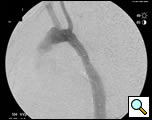

At our institution a dedicated CT angiogram of the chest was obtained to better define the morphology of the patient’s arch and aneurysm. This confirmed the finding of a saccular aneurysm just distal to the left subclavian artery takeoff. Because of the patient’s prior history of coarctation recurrence and repair, this was felt most likely to represent a pseudoaneurysm, possibly at the site of a patch repair. Aortic reconstructions of the CT angiogram showed no evidence for recurrence of the coarctation (Figure 2). There was, however, a size discrepancy in the diameter of the aorta above and below the aneurysm. The diameter of the aortic arch between the left carotid and left subclavian arteries was 13mm. The diameter of the descending thoracic aorta distal to the aneurysm was 23mm.